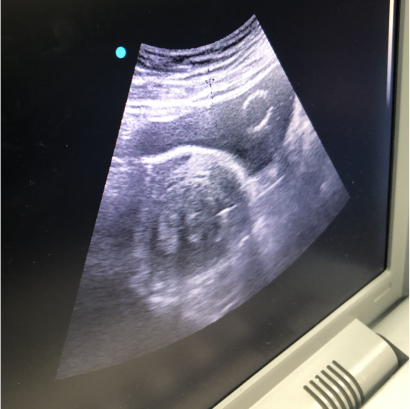

术后:

微波消融后肌瘤病灶内会发生凝固性坏死,即刻超声造影就可以看到病灶内没有造影剂充填。磁共振增强扫描病灶内呈现充盈缺损,增强后呈黑色区域,表示病灶坏死区域。坏死的病灶随时间推移,会逐渐萎缩吸收,子宫体积也会有一定的缩小,从而使痛经、月经量多等临床症状得到缓解和改善。